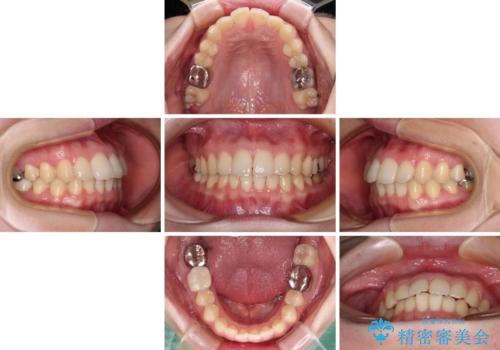

- 上下歯列全体のデコボコを気にして来院された患者様です。

主に下顎歯列全体の後方移動とIPR(歯と歯の間を削る)によってデコボコが解消するように設計し、インビザラインにより治療を行うこととしました。

1年半程度で終了するのではないかと予想しましたが、途中1年以上の来院がなく、トータルで3年の時間がかかってしまいました。

前歯のデコボコはより改善することが望ましい状態でしたが、患者様の希望により終了することとなりました。